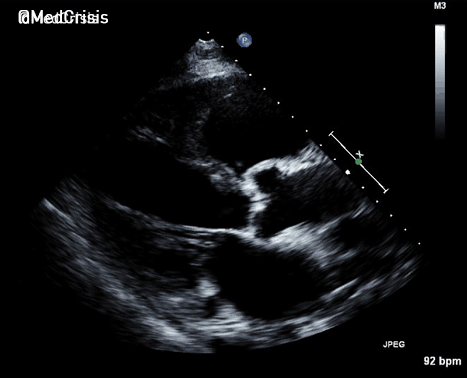

Parasternal long axis view: The septum is moving in an unusual jerky fashion and something can be seen in the RV. Despite left ventricular function appearing reasonable, the aortic valve is not opening much suggesting cardiac output is low.

Parasternal short axis: There is a large ventriculo-septal defect in the infero-septal LV. The right ventricle is severely impaired.

The LV function is hyperdynamic. The infero-basal septum is tethered near the mitral and tricuspid valves but highly mobile, creating a large VSD. The right ventricular free wall appears to bulge out and the RV is almost akinetic.